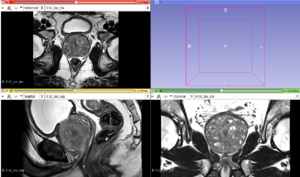

MRIs of the prostate (axial, sagittal and coronal volume)

For prostate lesion assessment, MRI volumes in sagittal, coronal and axial orientation are acquired. The goal is to segment the prostate in these volumes and fuse the segmentations in order to obtain better accuracy, especially in the apex and base regions (compared to segmentations obtained only on axial volumes).